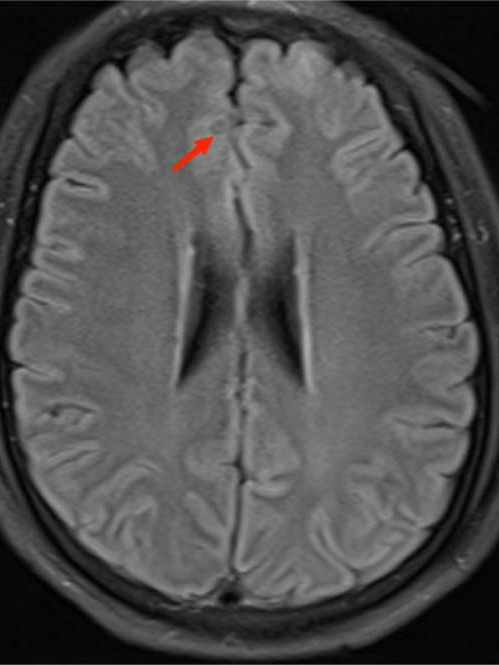

得到这条线索后,ICU 医生立即为李先生进行一系列脑部检查。最终,李先生头颅 MR 显示其脑内有寄生虫感染!明确诊断为脑囊虫病!